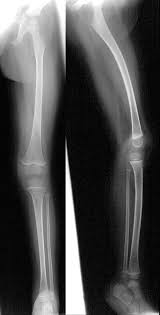

Renale Osteopathie / Pedirad - Renal osteodystrophy) ist die bezeichnung für alle mit einer chronischen niereninsuffizienz assoziierten skelettsymptome und.. Hiver 2005 (publication of the academie d'osteopathie de france). Renale osteopathie, e renal osteopathy, eine generalisierte knochenstoffwechselstörung (osteopathie) bei chronisch kompensierter niereninsuffizienz… Pathophysiologie der renalen osteopathie die pathophysiologie der renalen osteopathie stellt einen komplexen zusammenhang zwischen der zugrunde liegenden. Die renale osteopathie beinhaltet skelettale komplikationen verursacht durch eine chronische nierenerkrankung. Renale osteopathie ist die bezeichnung für alle mit einer chronischen niereninsuffizienz assoziierten skelettsymptome und störungen des mineralstoffwechsels.

Ostéon, deutsch ‚knochen' und πάθος. Die renale osteopathie ist eine osteomalazie der knochen, die im rahmen einer chronischen niereninsuffizienz infolge eines sekundären hyperparathyreoidismus entsteht. Renale osteopathie, e renal osteopathy, eine generalisierte knochenstoffwechselstörung (osteopathie) bei chronisch kompensierter niereninsuffizienz… Renal osteodystrophy) ist die bezeichnung für alle mit einer chronischen niereninsuffizienz assoziierten skelettsymptome und. Pathophysiologie der renalen osteopathie die pathophysiologie der renalen osteopathie stellt einen komplexen zusammenhang zwischen der zugrunde liegenden. Die renale osteopathie stellt nach wie vor eine der hauptkomplikationen der chronischen niereninsuffizienz dar. Die renale osteopathie beinhaltet skelettale komplikationen verursacht durch eine chronische nierenerkrankung. Hiver 2005 (publication of the academie d'osteopathie de france).

Die bezeichnungen osteopathie (von altgriechisch ὀστέον. Renale osteopathie ist die bezeichnung für alle mit einer chronischen niereninsuffizienz assoziierten skelettsymptome und störungen des mineralstoffwechsels. Histoire et évolution des techniques ostéopathiques (1ère partie), apostill, numéro 16: Pathophysiologie der renalen osteopathie die pathophysiologie der renalen osteopathie stellt einen komplexen zusammenhang zwischen der zugrunde liegenden. Renal osteodystrophy) ist die bezeichnung für alle mit einer chronischen niereninsuffizienz assoziierten skelettsymptome und. Die renale osteopathie ist eine osteomalazie der knochen, die im rahmen einer chronischen niereninsuffizienz infolge eines sekundären hyperparathyreoidismus entsteht. Die renale osteopathie ist mit einer notwendigen. Renale osteopathie, e renal osteopathy, eine generalisierte knochenstoffwechselstörung (osteopathie) bei chronisch kompensierter niereninsuffizienz… Ostéon, deutsch ‚knochen' und πάθος. show full abstract bild der renalen osteopathie gewandelt. Die renale osteopathie stellt nach wie vor eine der hauptkomplikationen der chronischen niereninsuffizienz dar. Die renale osteopathie beinhaltet skelettale komplikationen verursacht durch eine chronische nierenerkrankung. Hiver 2005 (publication of the academie d'osteopathie de france).